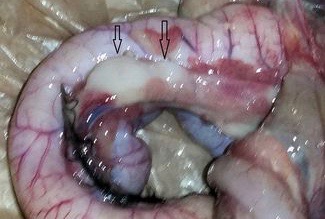

Gizzard and intestine, both with tumors:

Normally this is when I would stop seeing tumors. All of my birds that died before this one had tumors on, or in, the intestines and liver. A few had them on/in the gizzard. Unfortunately that was not the case with this pullet. I continued to find tumors, some on/in her heart.